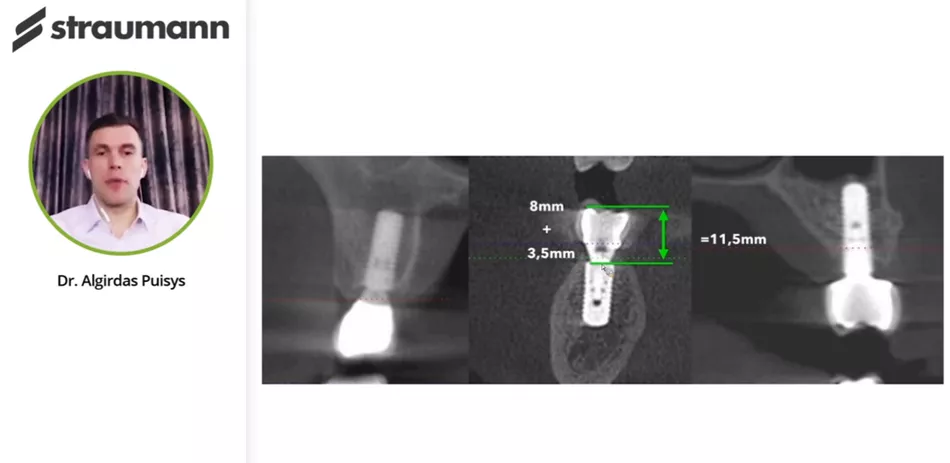

Campus Live Webinar with Dr. Algirdas Puisys: Crestal bone stability after immediate implant placement in molars

• Immediate implant placement in molar area

• 3D positioning of the implant